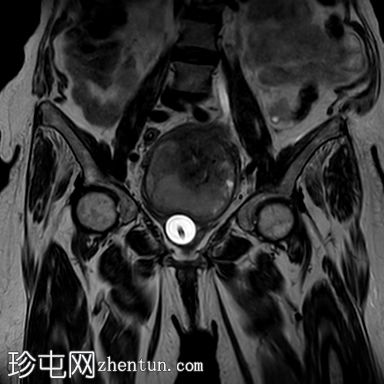

冠状位

T2

3.jpg

子宫呈U形,宫底轮廓消失,宫底突出至扩张的阴道内,宫颈位于内翻的宫底上方(II级子宫内翻):

宫底处可见阴道内可见边界不清、分叶状实性肿块,明显扩张阴道壁,阴道壁完整。

肿块最大轴向及头尾径约为 9.7 x 9.6 x 9.5 cm,T1 加权像呈低信号,T2 加权像呈中/高信号,伴有扩散受限和不均匀增强。

左侧附件复合体病变,包含实性和囊性成分,轴向径约为 5.3 x 4.7 cm。实性成分 T1 加权像呈低信号,T2 加权像呈中信号,伴有扩散受限和增强。

检查结果显示为 II 级子宫内翻,子宫底可见一巨大肿瘤性实性肿块,该肿块延伸并扩张了阴道,具体情况如上所述。

左侧附件复杂肿瘤性病变。